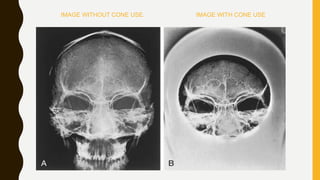

The document discusses the control of scattered radiation in X-ray imaging, covering topics such as types of scattered radiation, devices to limit beam exposure, and techniques for improving image quality. It highlights the disadvantages of scattered radiation and presents solutions like filters, collimators, and grids designed to enhance contrast and reduce patient radiation dose. The document also details various filtration methods and grid types that help minimize the impact of scatter on radiographic images.